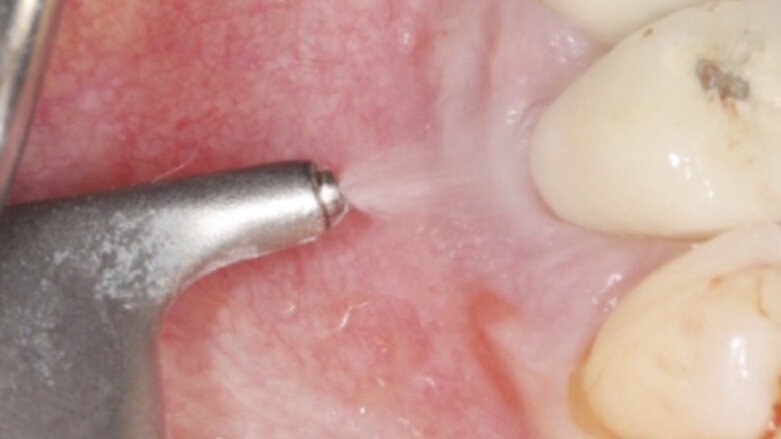

İşte bu dönemde implant bakımı konusunda kendimi eğitmek için bir yolculuğa başladım. İmplant şirketleri implant yerleştirme veya ameliyat sonrası komplikasyonlarla başa çıkma konusunda birçok kurs sunmalarına rağmen, koruyucu bakım modelinde büyük bir açık vardı. Bu yüzden, implant bakımı hakkında 20 dakikalık bilgi elde etmek için bazen 2 gün süren konferanslara katılmaya başladım. İmplant bakımı üzerine yapılan kurslara katılmak için Amerika ve İsviçre'ye gittim. Katıldığım tüm farklı eğitimlerin ortak bir noktası vardı ve bu AIRFLOW teknolojisi idi.

Bu noktada, hem genel bakım periodontal tedavi hem de implant bakımı için AIRFLOW kullanımı konusunda İsviçre Diş Akademisi’nin eğitim kursuna katıldım. Bu bilgiler ışığında AIRFLOW teknolojisini iş akışımıza dahil etmenin finansal faydalarını tartışmak üzere bir toplantı düzenledim. AIRFLOW teknolojisini ve GUIDED BIOFILM THERAPY protokolünü uygulamaya koyduğumuzda, 1 saatlik randevu süreleri 45 dakikaya inebilecek ve bu da günlük hasta sayısını iki katına çıkartabilecekti. Bu, haftada 8 hastaya eşittir ve bu da yılda 384 hastaya denk gelir. Bunu dolar değerine koyduğunuzda, bu herhangi bir klinik için çok büyük bir avantajdır. İşverenim bu yeni teknolojiyi heyecanla karşıladı ve büyük bir hevesle kabul etti.

Bir sonraki hafta, EMS AIRFLOW Prophylaxis Master cihazım geldi ve GUIDED BIOFILM THERAPY [GBT] yolculuğum başladı. İlk günden itibaren çok hoşuma gitti. Hastalarım daha mutlu ve dişleri daha az müdahale gerektiriyor, bu sayede de uzun dönemde periodontal cep derinliklerine yapılan müdahaleleri ve kök modifikasyonlarını azaltıyor.